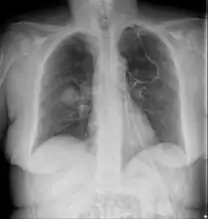

Imaging is often performed, such as CT scan of lungs and sinuses.[38] Signs on chest CT scans, such as nodules, cavities, halo signs, pleural effusion and wedge-shaped shadows, showing invasion of blood vessels may suggest a fungal infection, but does not confirm mucormycosis.[16] A reverse halo sign in a person with a blood cancer and low neutrophil count, is highly suggestive of mucormycosis.[16] CT scan images of mucormycosis can be useful to distinguish mucormycosis of the orbit and cellulitis of the orbit, but imaging may look identical to those of aspergillosis.[16] MRI may also be useful.[39]

Chest X-ray: likely fungal infection left lung in an immunocompromised person